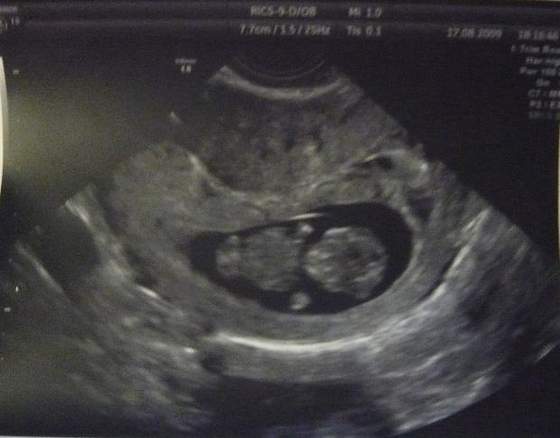

:-)a to moj maly łobuz... no w sumie nie taki maly bo chyba przez to ze wciagnal braciszka to ma az 7,7 cm;-) szkoda ze drugiego juz nie ma